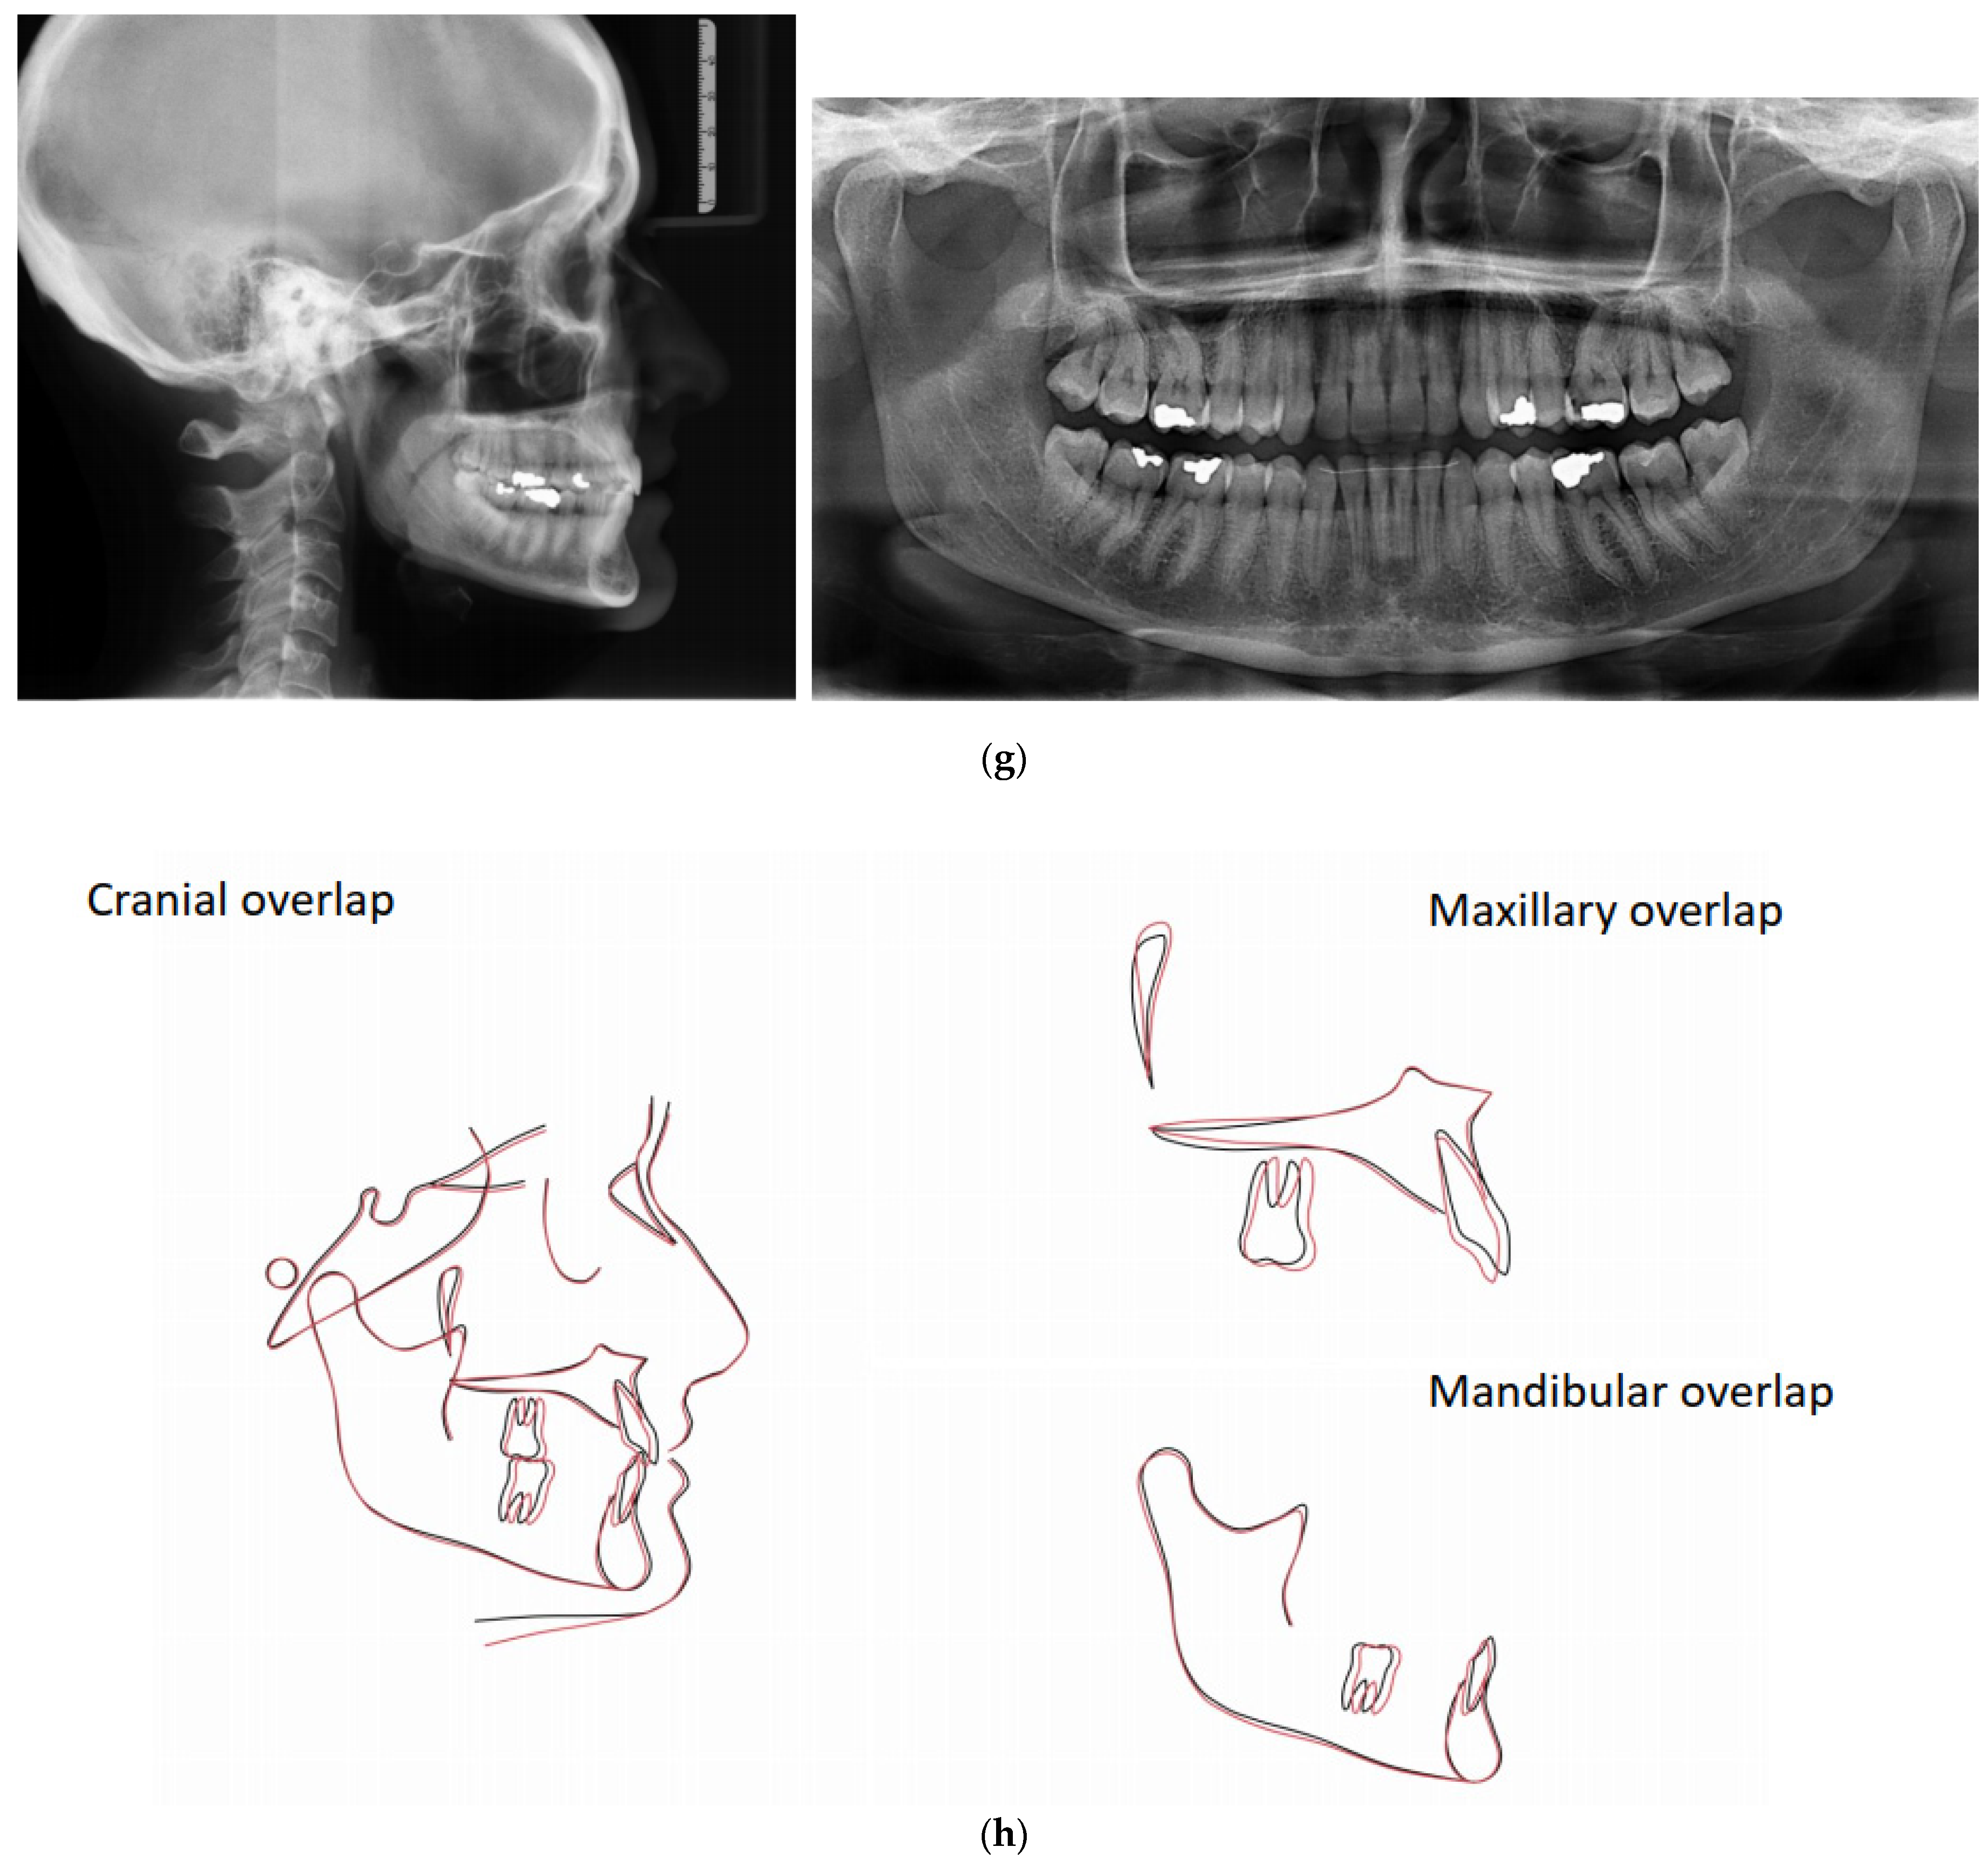

4.1. Case 1: Class II Division 2 with a Deep Bite